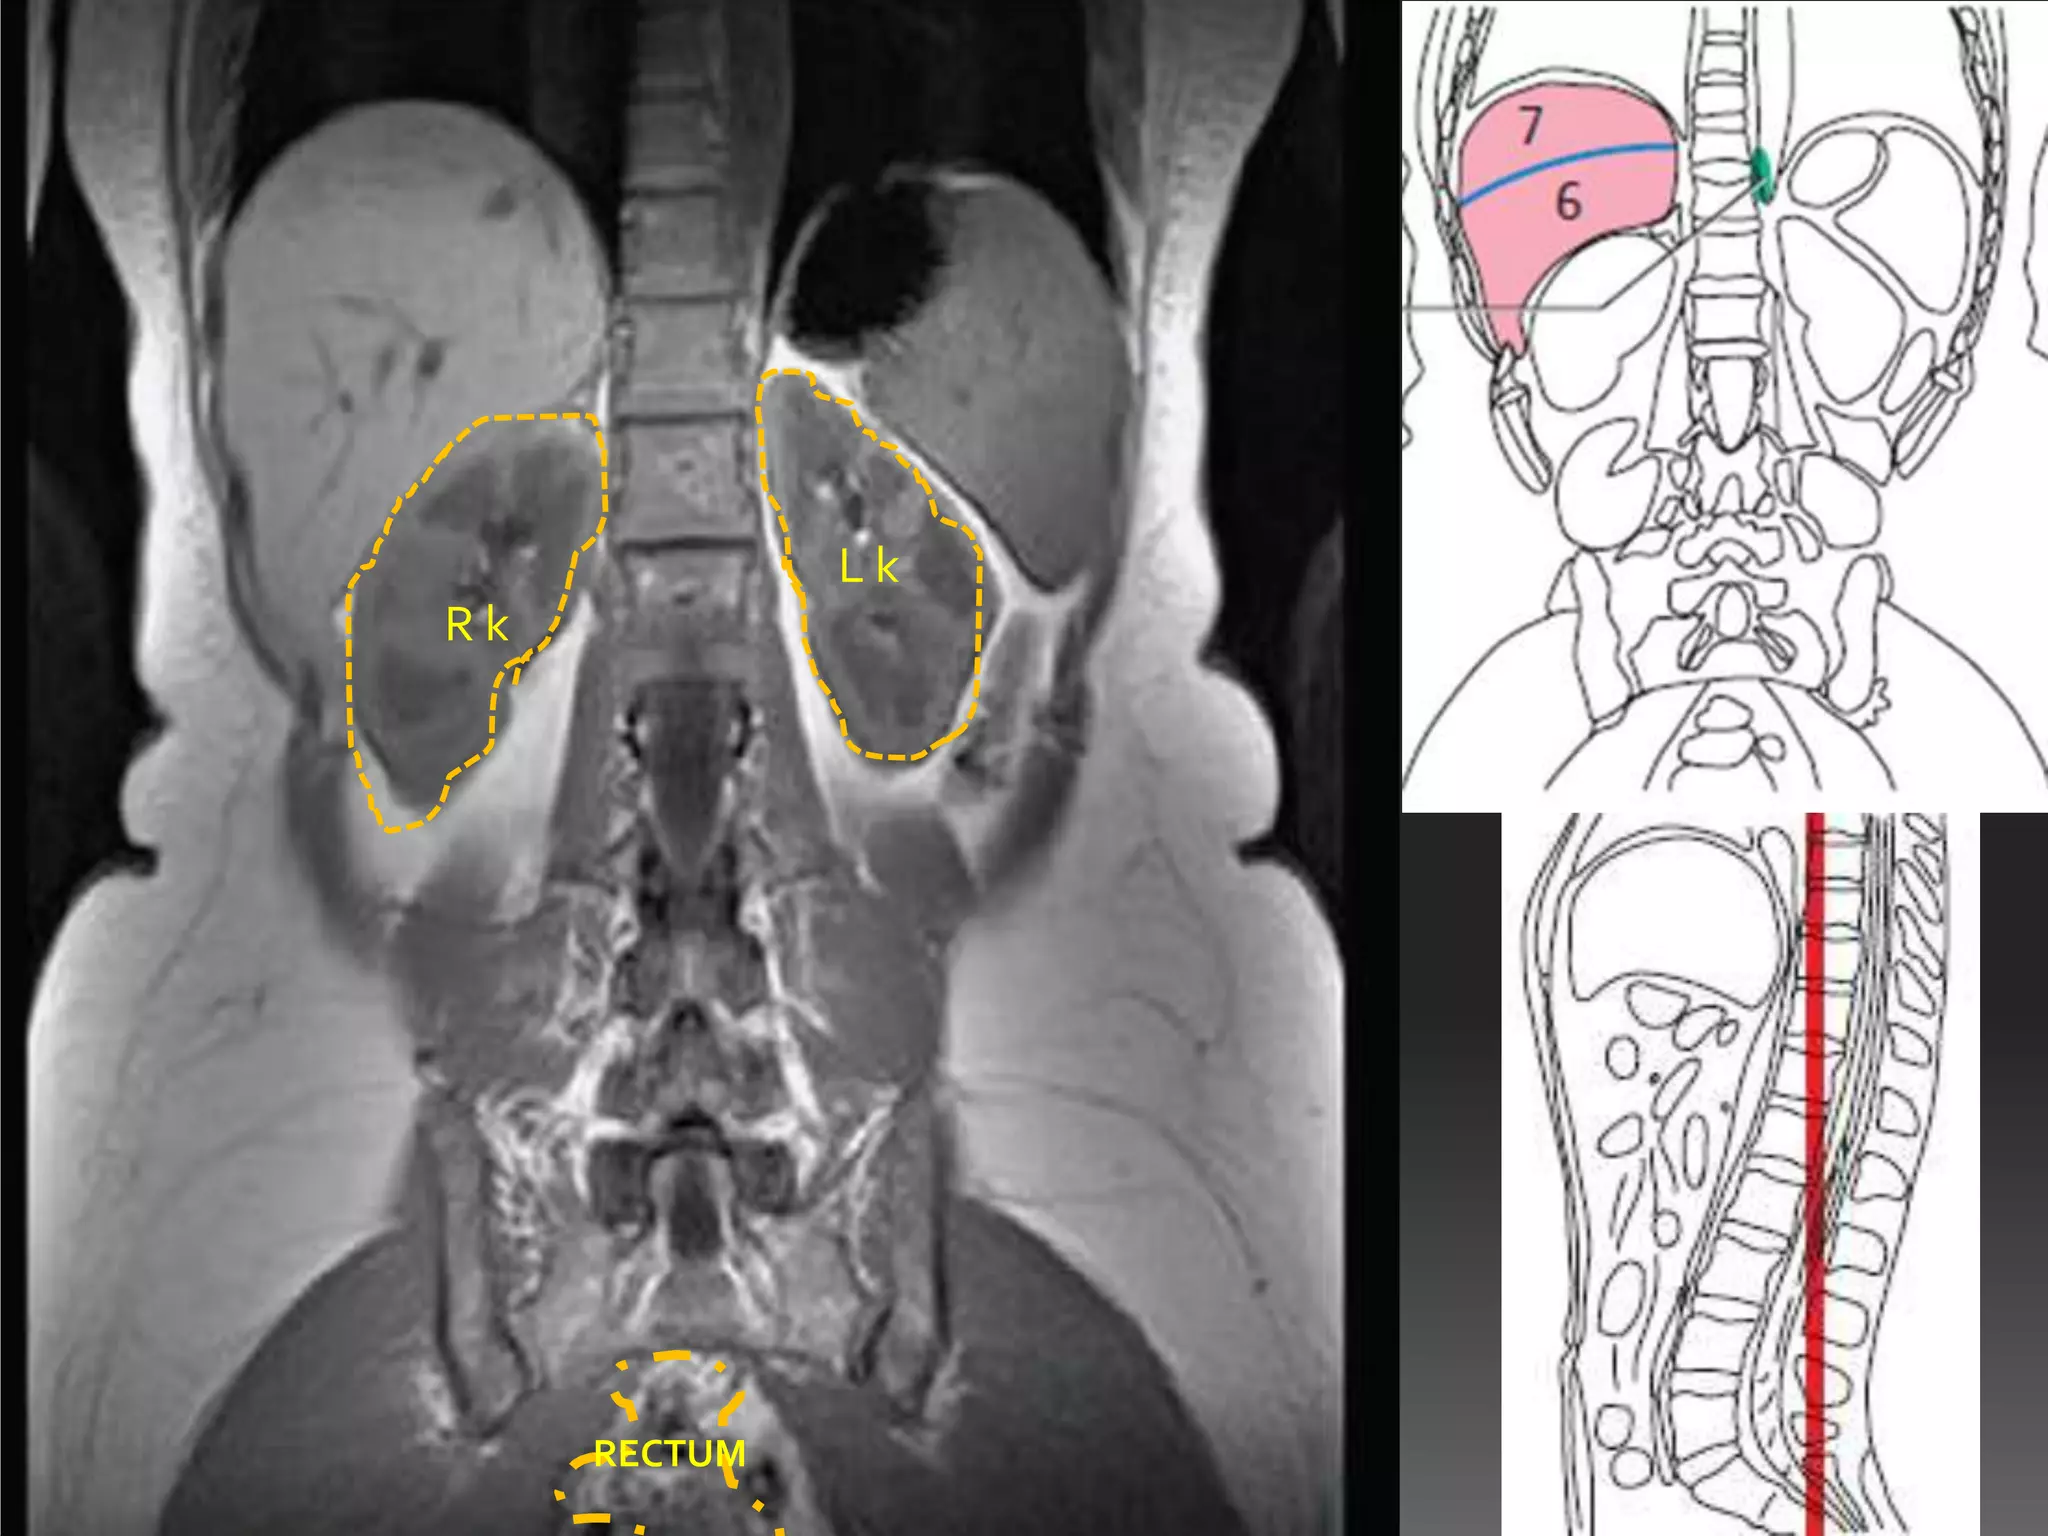

Lk

Rk

RECTUM